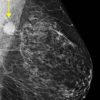

Ung thư vú

Ung thư vú - Ảnh 2

» Thông tin: Nữ giới – 51 tuổi.

» Lâm sàng: Khối tuyến vú.